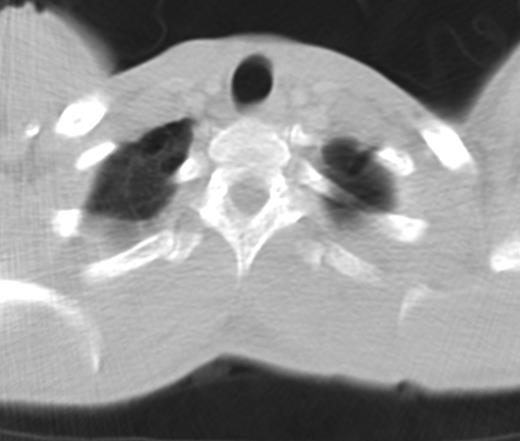

During hospitalization a chest computed tomography (CT) was performed and revealed the presence of blebs at the apices of both upper lungs (Fig. 4). After recovery the patient was referred to a tertiary center for an elective video-assisted thoracoscopic surgery intervention (VATS). Three years after, no recurrence of pneumothorax took place and the patient remains healthy.

CT image showing bilateral blebs on the apices of the upper lobes.